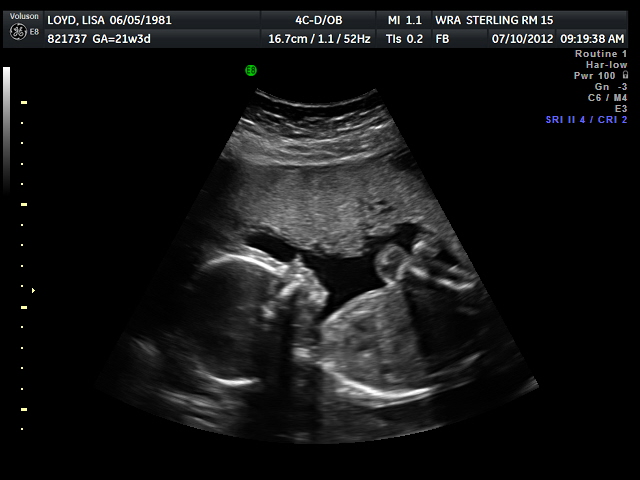

And we were right!!! You were finally cooperating and we were able to find out that you are a....

Sorry, I can't say just yet, we have to wait until after this Saturday at our Annual Christmas in July before we can say anything publically. You're daddy and I are so excited though, we got to see your little face and feel so blessed that everything that the ultrasound showed was healthy and good.

Aren't you cute?